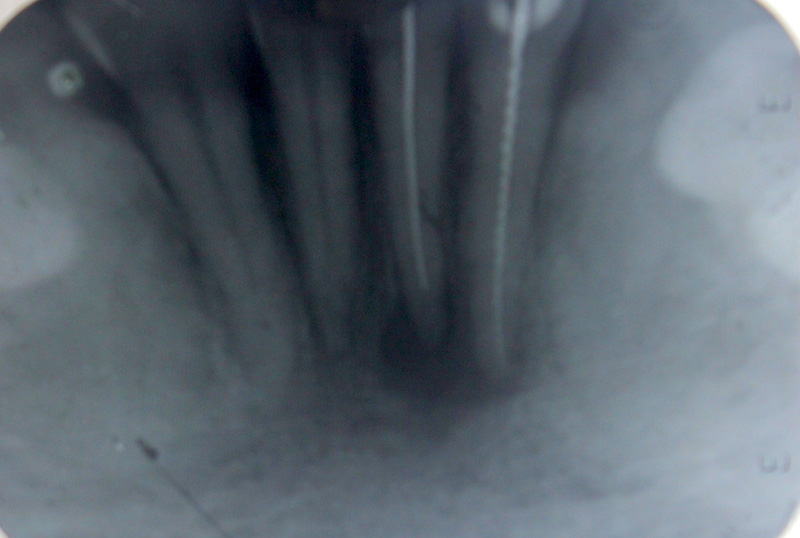

Bilateral Direct Sinus Lifts